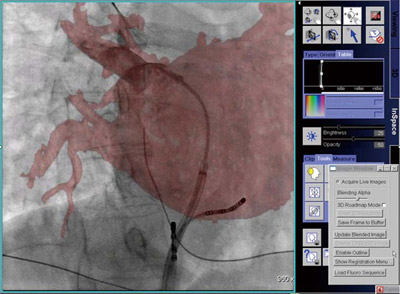

syngo iPilot(図3)

syngo iPilot”は,作成した3次元画像と透視中のライブ画像を,リアルタイムで重ね合わせ表示する3Dロードマップ機能である。あらかじめ手技に必要な領域を3D画像化しておき,必要に応じて透視画像とオーバーレイ表示することで,デバイスを迅速かつ安全に誘導することができる。従来は,頭部血管などに使用されているが,上記のsyngo InSpace EPによる左心房3D画像を透視画像上に投影させることで,アブレーションカテーテルの正確な留置を支援する。透視画像と3D画像は相互に連動しており,Cアーム角度,画像サイズ,寝台位置などの変更にリアルタイムで追従するため,心房細動のAF治療のワークフローを改善させることもできる。

図3 syngo iPilot